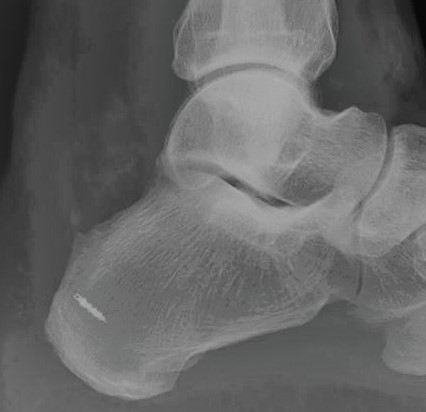

Häufig kommt es neben der Haglund-Exostose zur Ausbildung eines dorsalen (an der Rückseite des Fußes liegenden) Fersenspornes. Hierbei verknöchert der Ansatz der Achillessehne am Fersenknochen. Es entsteht daraufhin eine schmerzhafte Vorwölbung am hinteren Rand des Fersenknochens.

Ein Röntgenbild des oberen Sprunggelenkes ist zur Darstellung der Haglund-Ferse und des dorsalen Fersenspornes ausreichend. Um zudem Einrisse der Achillessehne nicht zu übersehen, ist die Anfertigung eines MRT-Bildes sinnvoll.

Liegt zusätzlich ein dorsaler Fersenporn vor, kann dieser bei einer Operation mit entfernt werden. Bei diesem Eingriff muss die Achillessehne teilweise vom Knochen abgelöst werden. Nach Entfernung des Spornes ist zur Rekonstruktion des Sehnenansatzes das Einbringen eines Knochenankers notwendig.